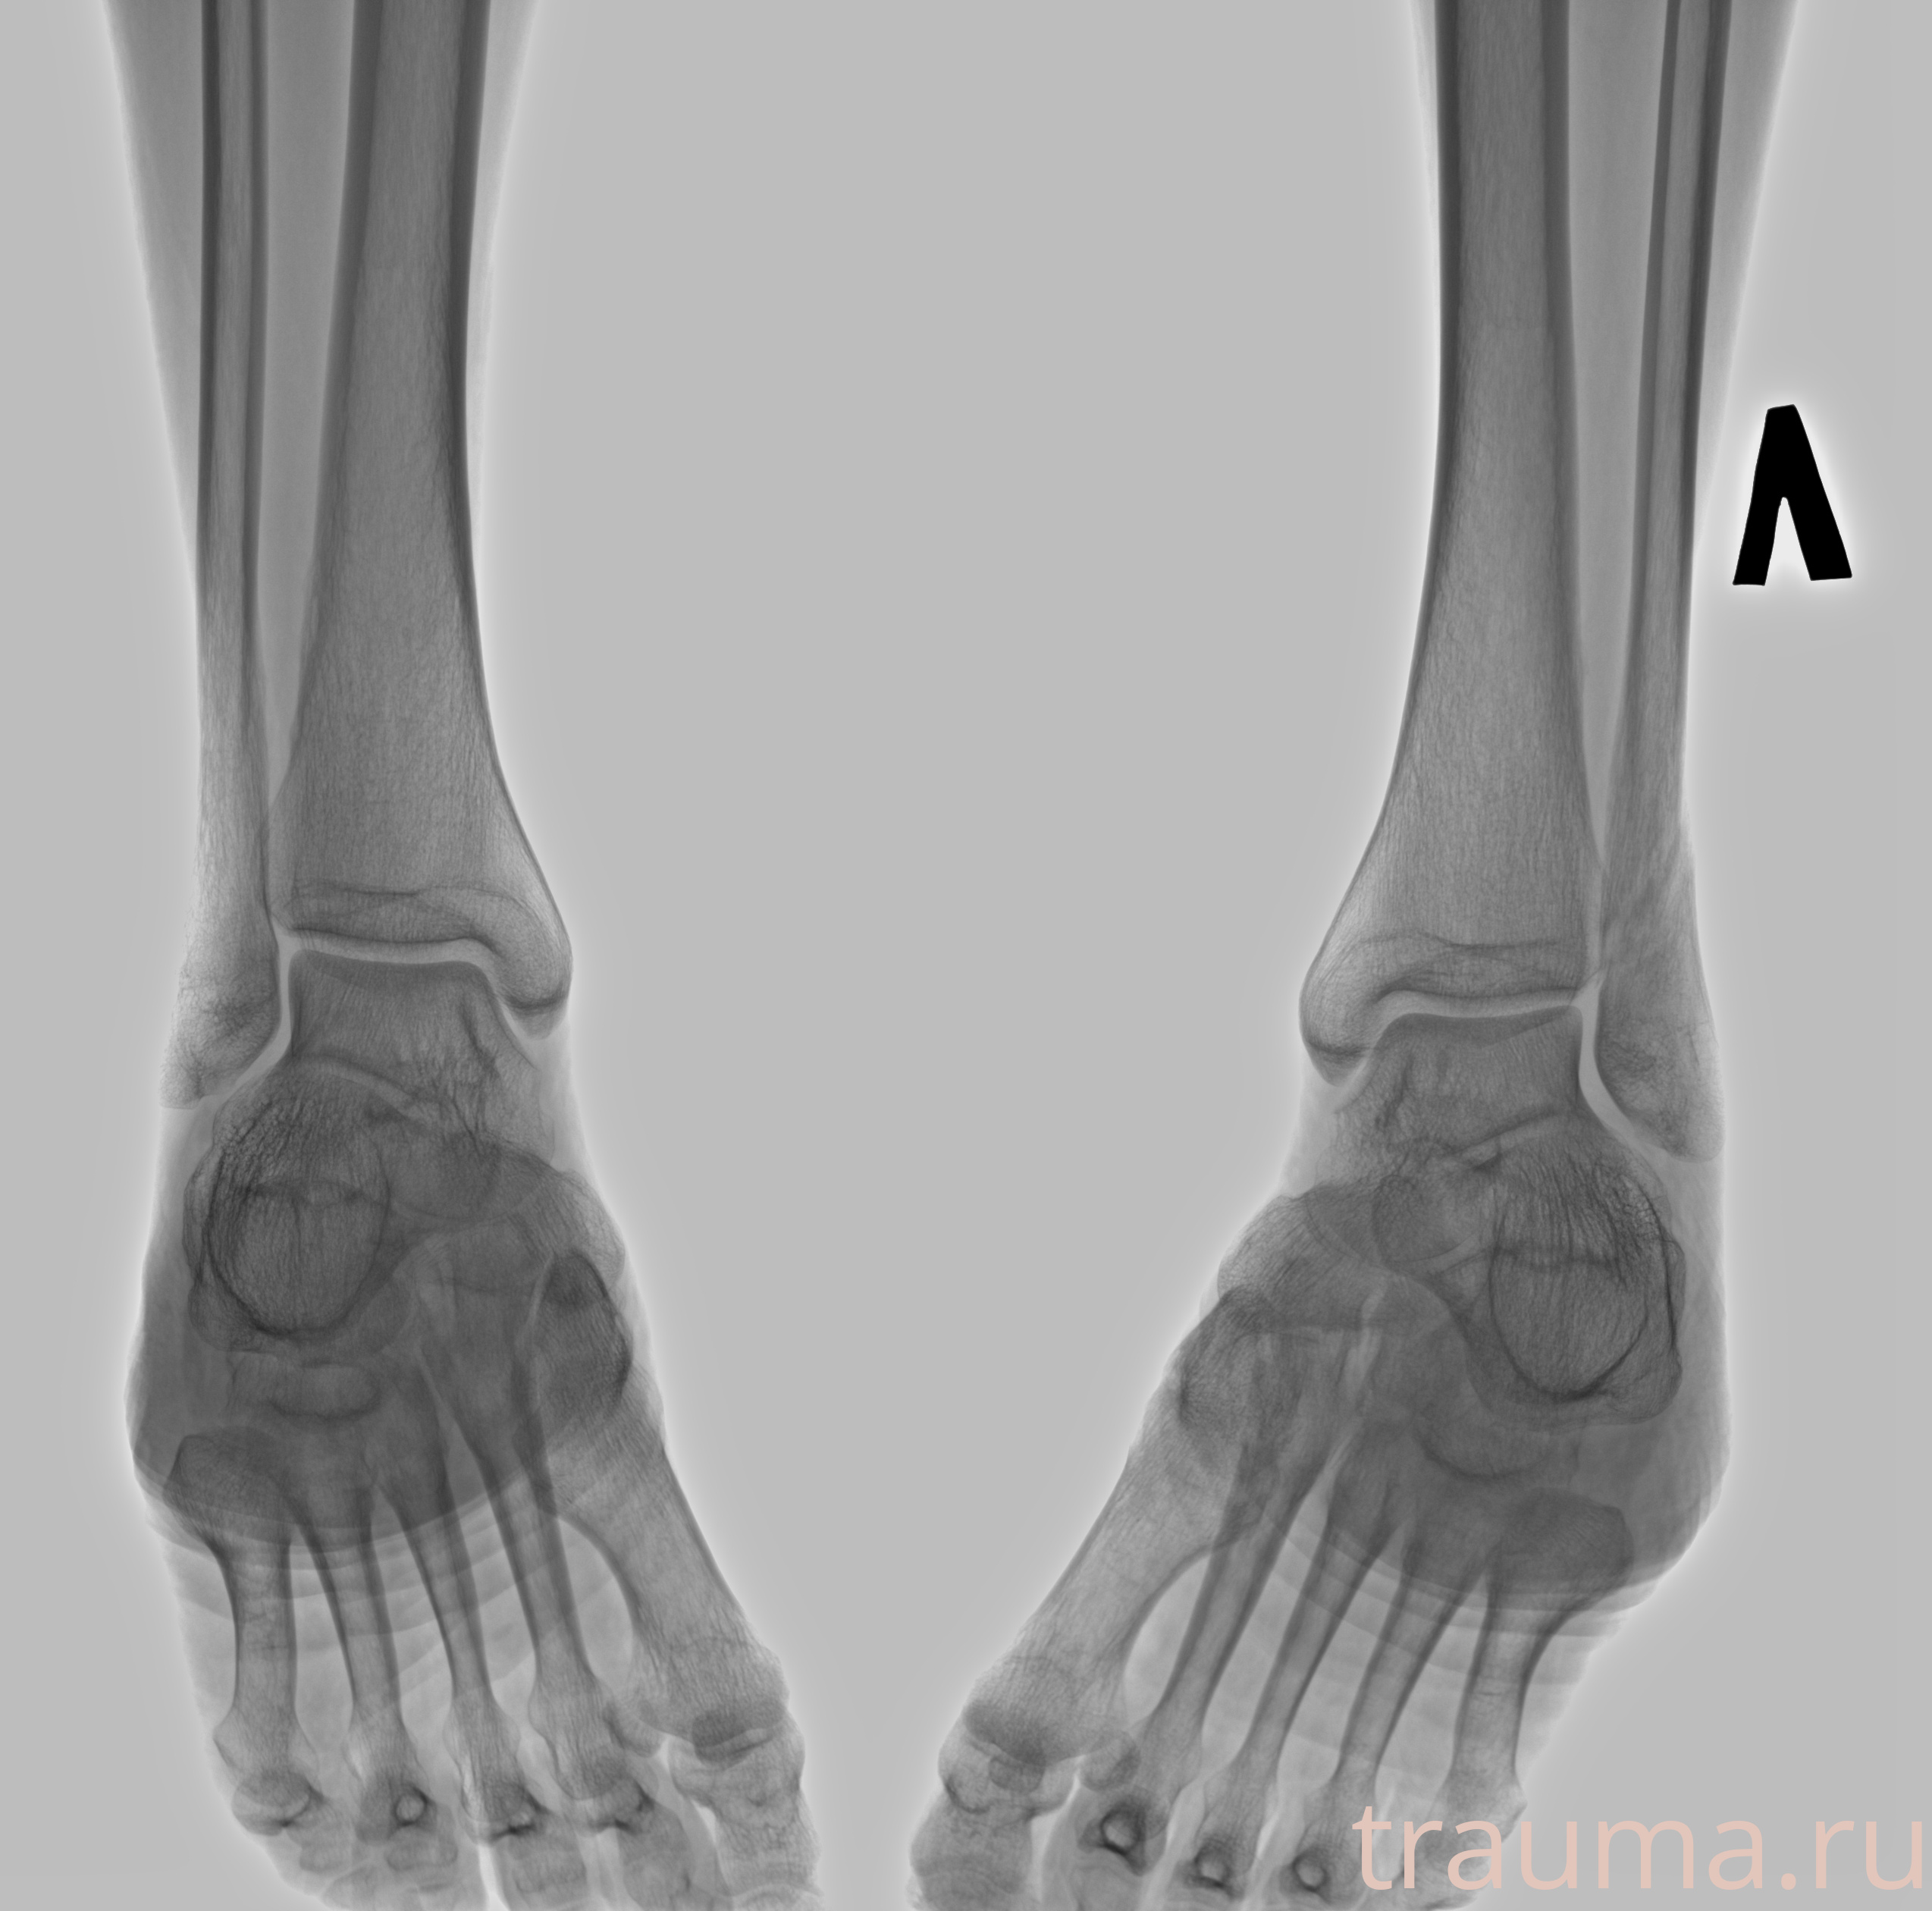

Рентгенограммы

Рентген на дому: по вашему адресу приезжает врач-рентгенолог, травматолог-ортопед с мобильным рентгеновским аппаратом, проводит диагностику травмы или заболевания, делает необходимые рентгенограммы, дает рекомендации по дальнейшему лечению. Получить качественные снимки в домашних условиях возможно благодаря уникальной методике, разработанной МосРентген Центром для института  Склифосовского

Яркость: 1   Контраст: 1   Инвертировать: 0 Увеличение: 1

Перетаскивайте мышь вверх/вниз для контраста, влево/право для яркости. Прокрутка колесом изменяет масштаб. Нажмите Сбросить для возврата к исходному изображению. При увеличении держите мышь в той области, которую хотите рассмотреть.